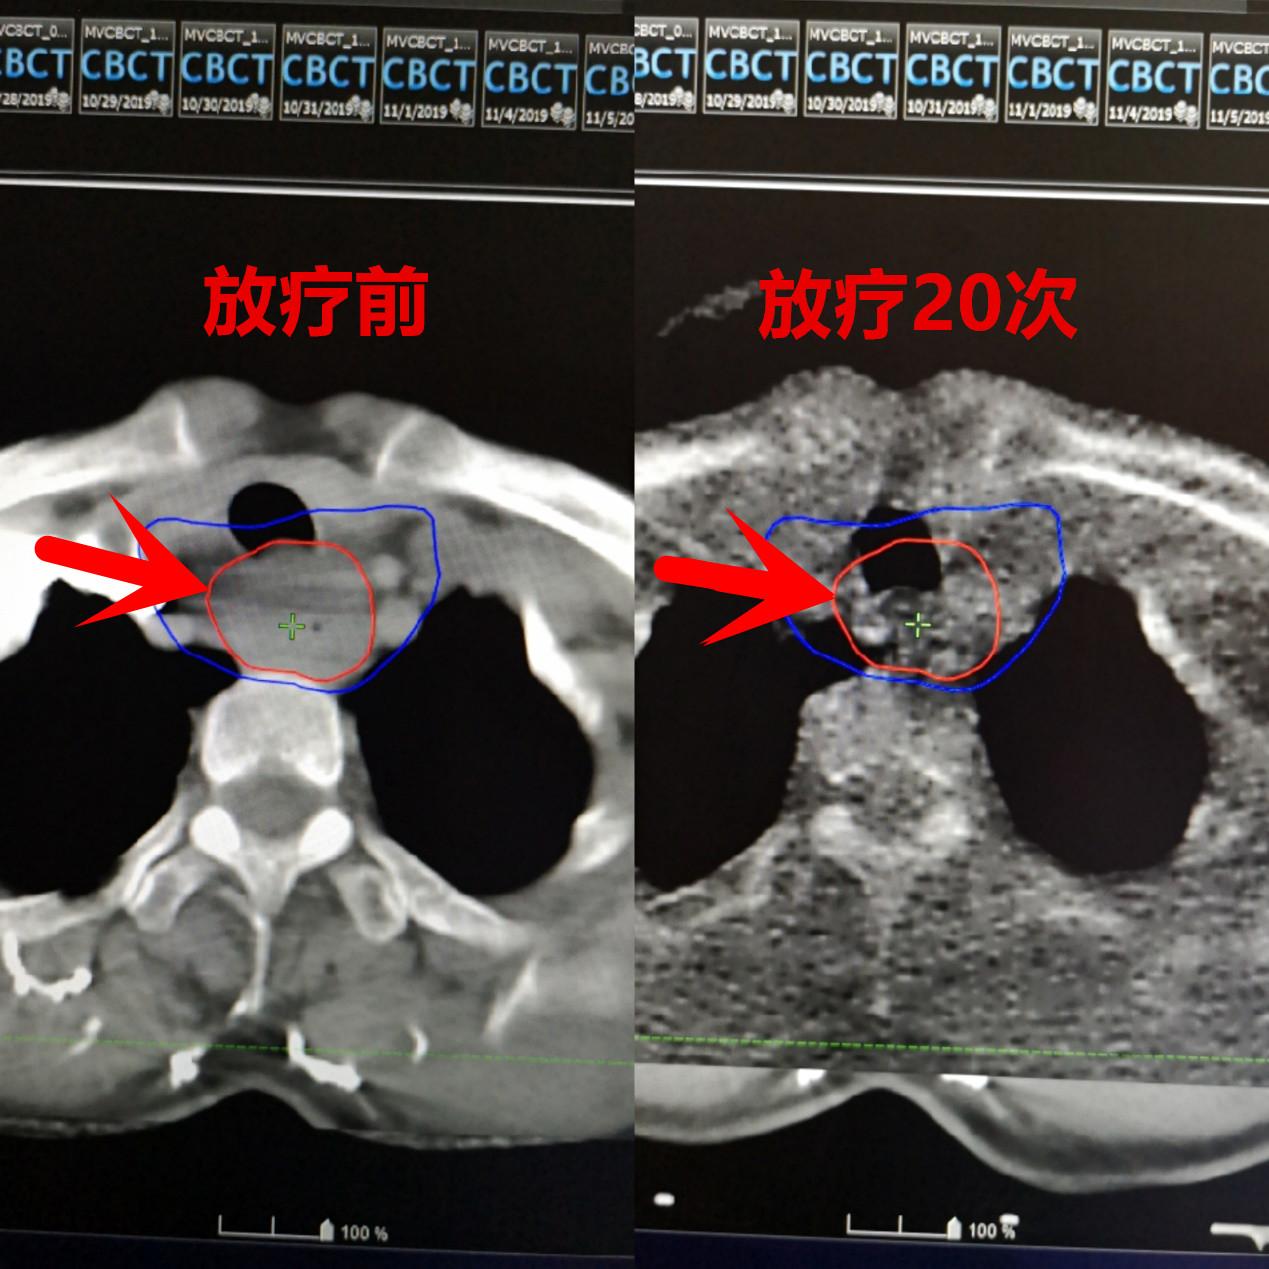

患者王先生,刚入院时只能进食清水,喝点小米粥都会咽不下去,还伴有颈部疼痛,非常痛苦,明显消瘦。食管镜检查证实为“颈段食管鳞癌”,位置较高不适合手术。经肿瘤中心讨论后决定给予放疗,治疗15次病人开始好转,逐渐可以进食稀饭,烂面条等半流质饮食。治疗结束后病人可以正常进食,疼痛也完全缓解,体重涨了20斤。

放疗前后对比图,肿瘤明显缩小